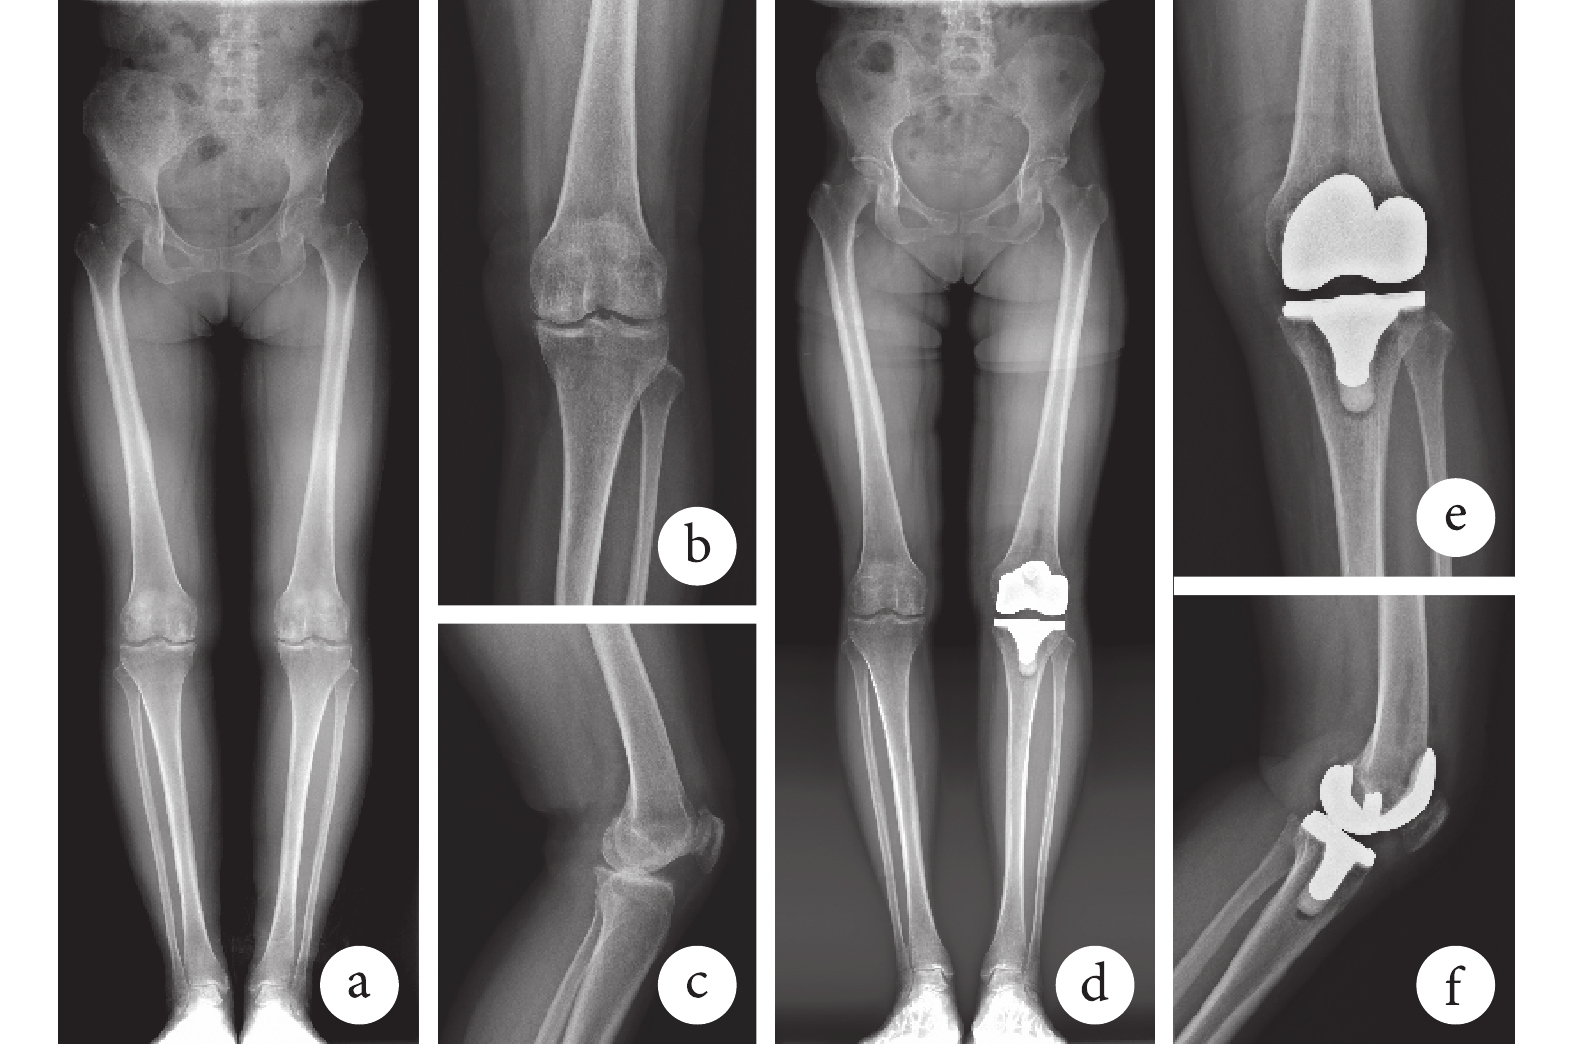

X線片復查示患者下肢力線均改善,膝關節假體位置良好,隨訪期間未出現假體松動、感染等嚴重不良事件。見圖1、2。術后6個月,機器人輔助手術組除LDFA與術前比較差異無統計學意義(P>0.05)外, HKA、MPTA和PPTA均較術前改善,差異有統計學意義(P<0.05);傳統手術組上述指標均較術前改善,差異有統計學意義(P<0.05)。上述指標兩組間手術前后差值比較,差異均無統計學意義(P>0.05)。見表2。

a~c. 術前;d~f. 術后6個月

Figure1. Full-length lower extremity X-ray films and knee anteroposterior and lateral X-ray films of a 60-year-old female patient with osteoarthritis of right knee in robot-assisted operation groupa-c. Before operation; d-f. At 6 months after operation